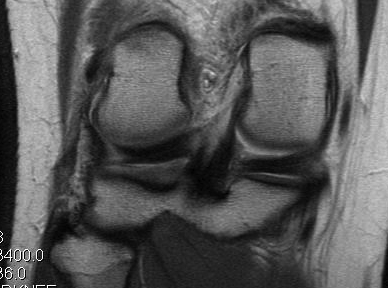

Lateral collateral ligament anatomy

Normal anatomy

Popliteus anatomy

Normal anatomy

Popliteofibular ligament anatomy

Normal anatomy